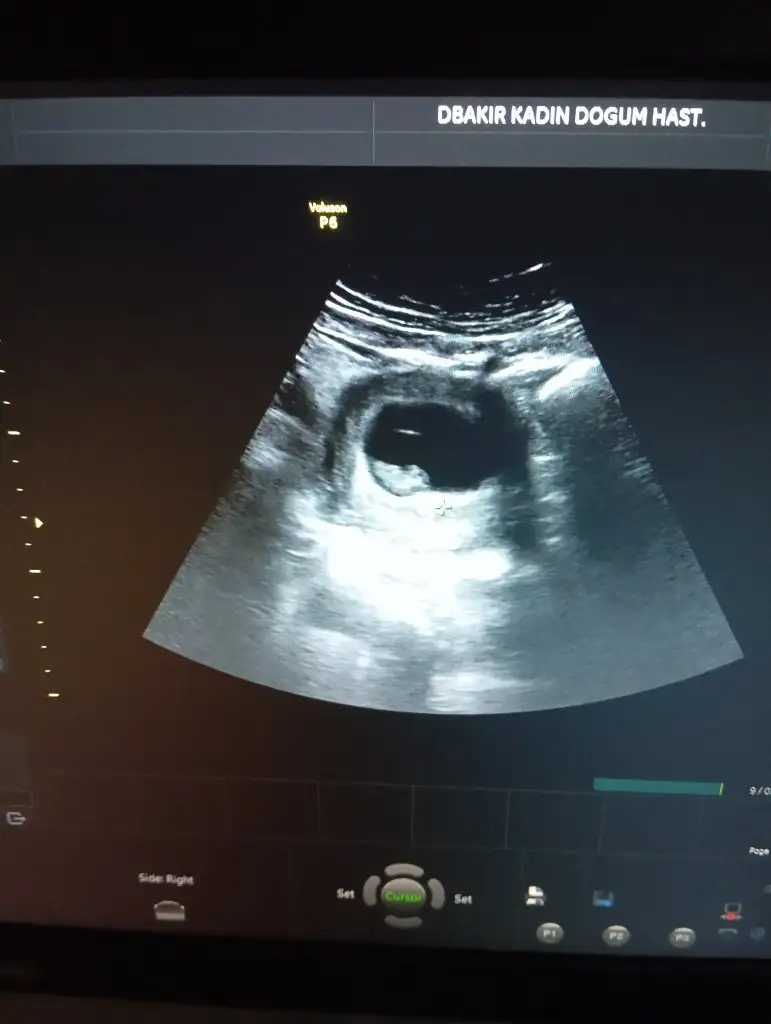

Bana da tahmin yaparmısınız

Eklentiler

• A6412A19-7D6F-4DC3-9149-FBE6D0210A9A.webp

A6412A19-7D6F-4DC3-9149-FBE6D0210A9A.webp

56,7 KB · Görüntüleme: 6